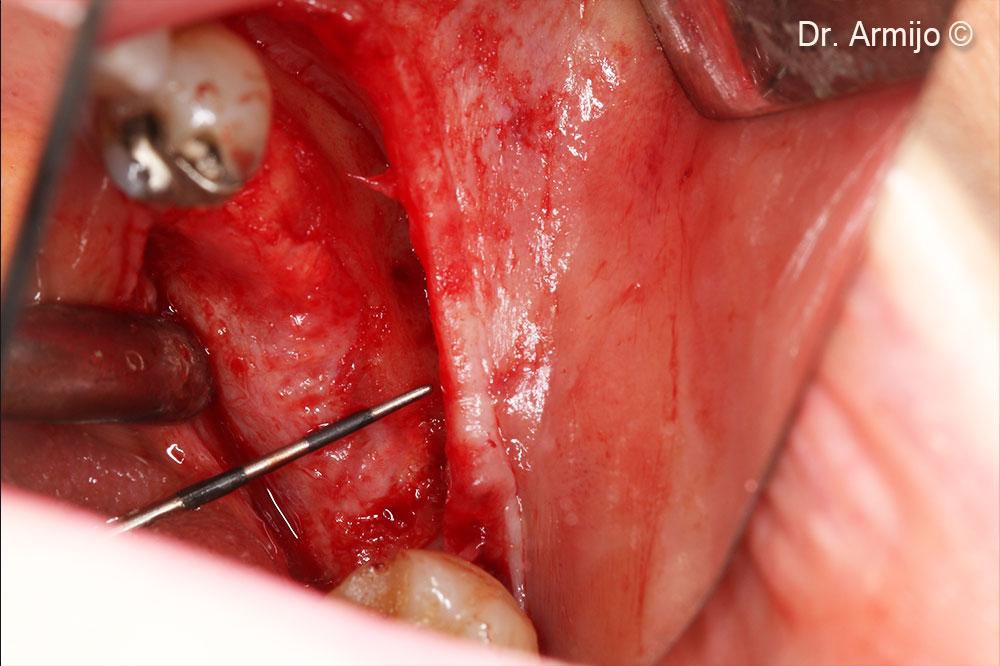

Detachment

Perforations down to the medullary bone.